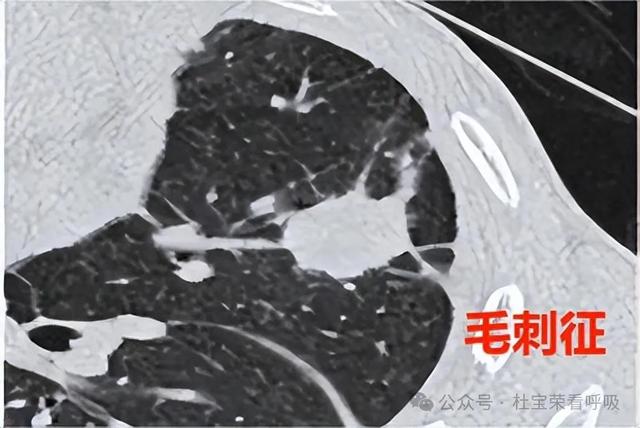

一、结节边缘光滑、无分叶或毛刺

俗话说:丑人多作怪!其实这句话也可以套用在肺结节上,肺结节的形态越不正常,长得越丑,其风险越高。而边缘清晰,类似“玻璃球”般光滑,无毛刺、分叶或胸膜牵拉的肺结节,表明其生长速度缓慢,对周围组织没有侵袭性,多为良性肺结节;